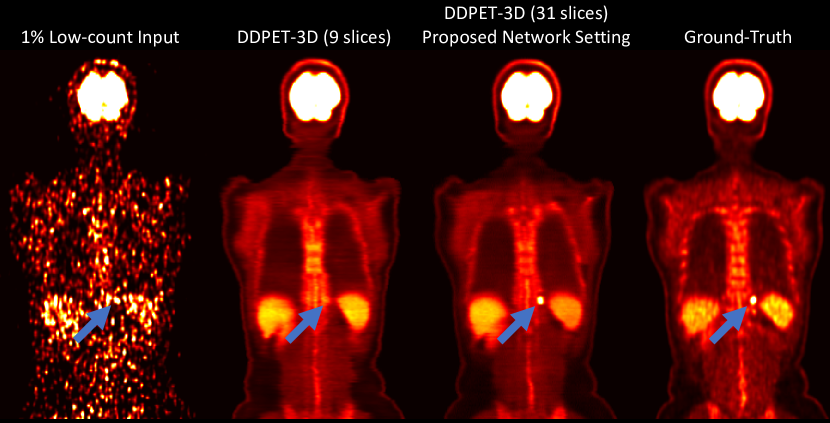

Impact of Number of Conditional Slices: We evaluated the DDPET-3D with different numbers of neighboring conditional slices. Three variants of DDPET-3D networks were trained using 9, 21, and 41 neighboring slices as conditional information. These networks are denoted as ”DDPET-3D ( slice)”, where is the number of conditioned neighboring slices. Results showed that performed the best in most quantitative metrics. Therefore, was used in this paper. Quantitative results are presented in Table III. As presented in Fig. 10, using more conditioned slices helped the network to recover some subtle details in the images (blue arrows in Fig. 10).

For comparison, we also extended the comparison diffusion models (DiffusionMBIR, TPDM, and DDIM), and re-trained them using neighboring slices as conditional information (denoted as DiffusionMBIR+2.5D, TPDM+2.5D, and DDIM+2.5D). Sample reconstruction results are presented in Fig. 11. Simply adding neighboring slices as conditional information does not necessarily lead to a better performance in other baseline models. Using the same testing patients in Table II, corresponding quantitative evaluations are presented in Table IV.